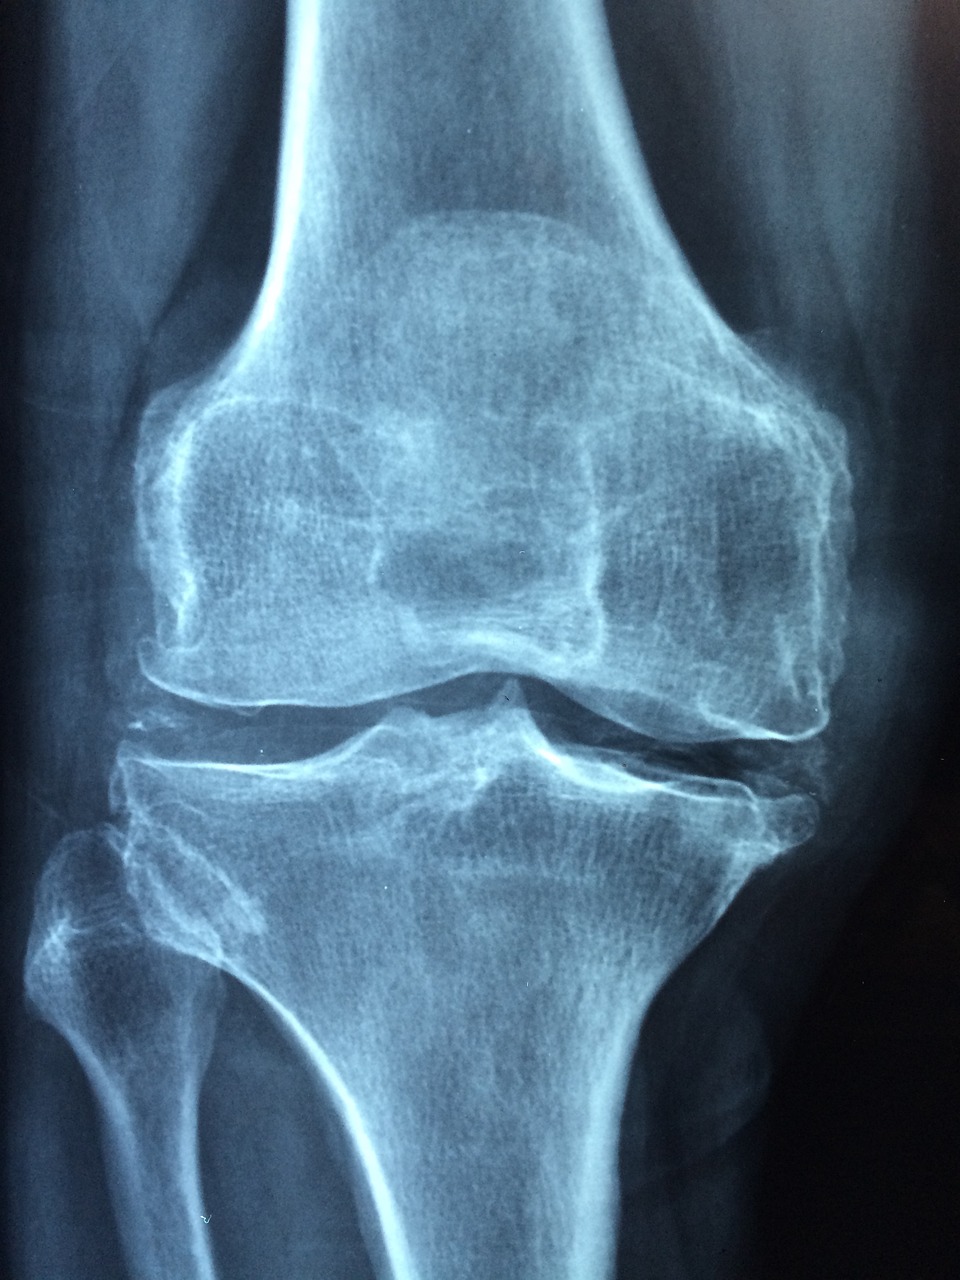

관절염은 관절에 영향을 주는 염증성 질환으로, 여러 다른 형태가 있습니다. 가장 흔한 두 종류는 오스테오아르트리티스(퇴행성 관절염)와 류마티스 관절염입니다. 관절염의 증상은 종류에 따라 다르지만, 일반적으로 다음과 같은 공통적인 증상들이 나타날 수 있습니다:

- 관절의 변형: 특히 류마티스 관절염 같은 염증성 관절염은 관절과 주변 조직의 손상으로 인해 관절이 변형되거나 비정상적인 모양을 취할 수 있습니다.

- 운동 범위 감소: 관절염이 진행됨에 따라, 관절의 운동 범위가 점차 감소할 수 있으며, 일상 생활에서의 움직임이 어려워질 수 있습니다.

관절염의 원인과 증상은 개인마다 다르며, 정확한 진단과 적절한 치료를 받는 것이 중요합니다. 초기에 적절한 치료를 시작하면 증상을 완화하고 관절의 손상을 늦출 수 있습니다. 만약 관절염 증상이 의심된다면 의사의 진료를 받는 것이 좋습니다.